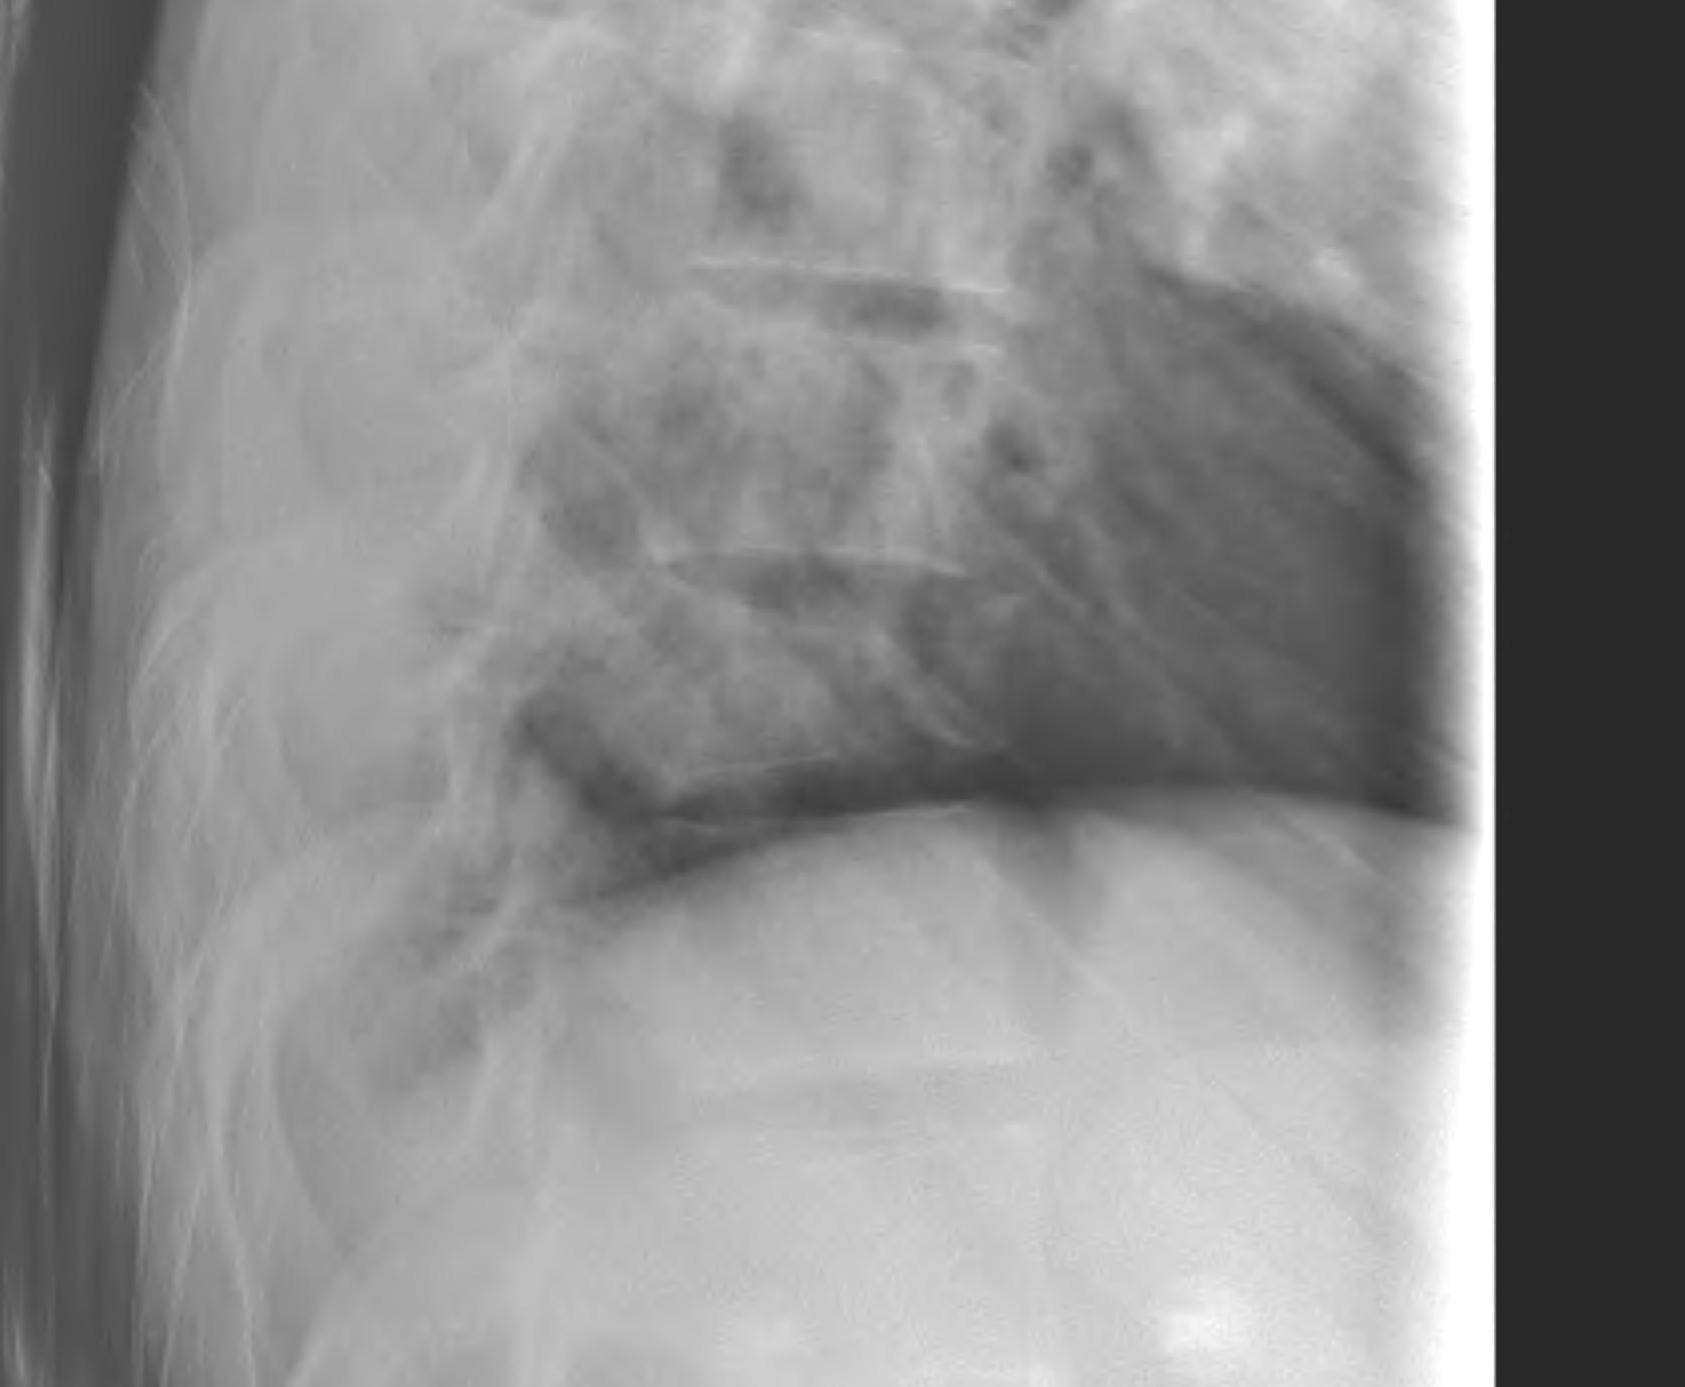

X-ray

- pedicle widening on AP

- posterior body height decreased on lateral < 50%